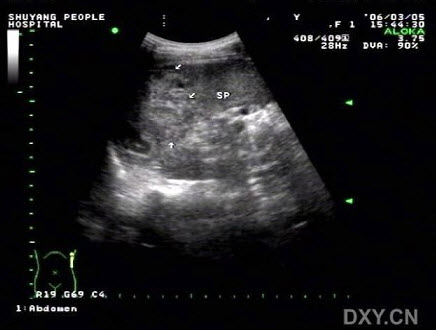

13、单项选择题

女,25岁,因急性胰腺炎禁食5天。声像图如图所示。结合超声声像图,诊断为()